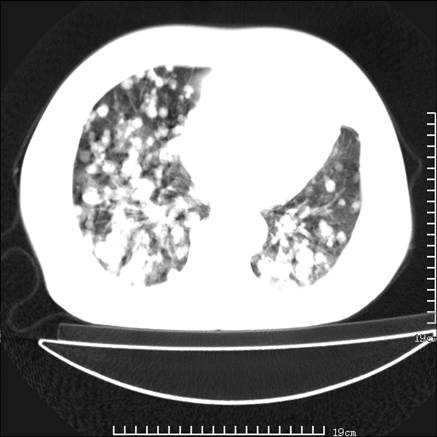

张男,75岁,干咳半年余,小便不利二年,b超检查前列腺增大,未见明显肿块;前列腺癌血生化检查多项指标明显增高。

双肺内多发转移瘤,纵膈淋巴结转移。来源前列腺?建议盆腔mri进一步检查。

双肺转移满了。

两肺广泛转移瘤。